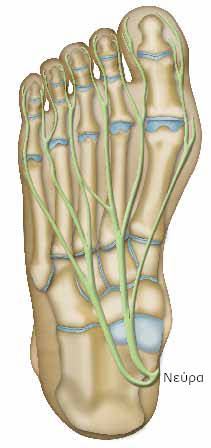

Τα νεύρα μεταφέρουν τις πληροφορίες στον οργανισμό, με τη μορφή ηλεκτρικού ρεύματος. Πολυάριθμα νεύρα περνούν από τους δακτύλους.

Τα νεύρα, όπως και τα καλώδια του ηλεκτρικού ρεύματος, περιβάλλονται από μια θήκη που τα προστατεύει και τα απομονώνει.

Ορισμένα νεύρα οδηγούν στην κίνηση των δακτύλων (κινητικά νεύρα). Άλλα (αισθητικά νεύρα) συμβάλλουν στην αισθητικότητα. Σας επιτρέπουν, για παράδειγμα να αισθάνεστε το άγγιγμα ή τον πόνο.